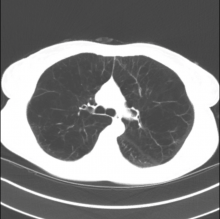

A 50-year-old woman with severe emphysema due to smoking underwent lung volume reduction surgery of her right upper lobe.

A subxiphoid incision measuring 2.5 cm was made, through which the telescope and video-assisted thoracoscopic instruments were introduced and the target lung was removed. Deflation of the target lung was facilitated by puncturing the lung with diathermy, though scissors may also be used. Excision was completed using reinforced staples that were administered utilizing a powered stapler. The authors recommend creating a pleural tent in upper lung volume reduction surgery to reduce air leaks. Finally, careful closure of the incision was performed, with the chest drain coming out through the subxiphoid incision.